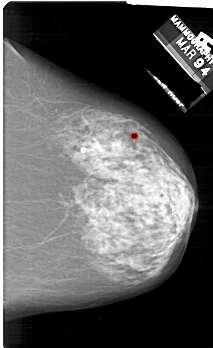

A_1829_1.RIGHT_CC

RIGHT_CC LINES 6601 PIXELS_PER_LINE 4036 BITS_PER_PIXEL 12 RESOLUTION 43.5 OVERLAY

FILE: A_1829_1.RIGHT_CC.OVERLAY

TOTAL_ABNORMALITIES 1

ABNORMALITY 1

LESION_TYPE CALCIFICATION TYPE PLEOMORPHIC DISTRIBUTION CLUSTERED

ASSESSMENT 4

SUBTLETY 3

PATHOLOGY BENIGN

TOTAL_OUTLINES 1

BOUNDARY